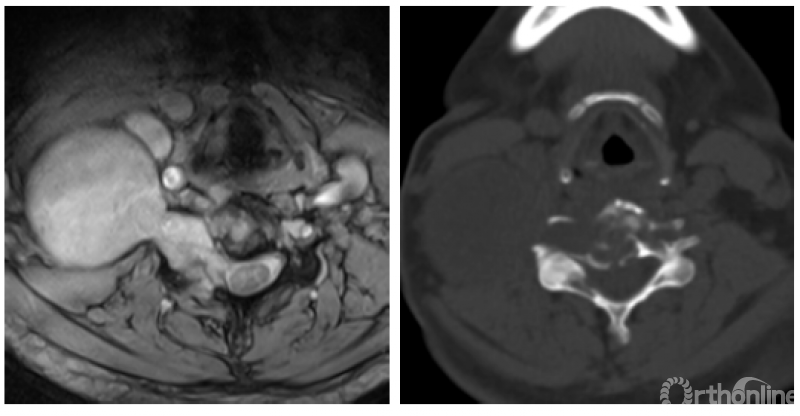

根据术前的影像学显示,肿瘤累及C3-4椎体、在左侧椎间孔形成软组织肿块包绕左侧椎动脉、C3和C4神经根,并且向椎管内和左侧颈长肌蔓延。肿瘤的恶性程度要求必须将肿瘤连同受累的所有结构作为一整块地切除。切除的范围不充分,切除过程中肿瘤的包膜有破损,都容易造成肿瘤的复发。但牺牲左侧的C3和C4神经根势必造成术后左侧膈肌麻痹;切除左侧椎动脉则有脑梗的风险。在充分评估肿瘤彻底切除的必要性、手术风险,以及和病人充分的沟通后,我们拟定了如下整块切除的手术计划。

首先从前方入路,切除C2-3和C4-5椎间盘及后纵韧带,切除C3和C4右侧横突孔,游离右侧的椎动脉,切断左侧椎旁肿瘤近端和远端的颈长肌,游离椎旁软组织的肿瘤。

随后,行后正中入路,做C1侧块,C2、C5、C6椎弓根螺钉固定。分块切除C3和C4没有被肿瘤累及的附件结构,将肿瘤在椎管内外的部分充分游离,,在硬膜外切断左侧C3和C4神经根。

最后再从前方原手术切口进入。切断左侧椎动脉、将C3、C4椎体及椎旁的肿瘤作为一整块地取出。C2-5椎体间放置3D打印人工椎体后用钛板固定。